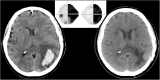

The capacity for functional restitution after brain damage is quite different in the sensory and motor systems. This series of presentations highlights the potential for adaptation, plasticity, and perceptual learning from an interdisciplinary perspective. The chances for restitution in the primary visual cortex are limited. Some patterns of visual field loss and recovery after stroke are common, whereas others are impossible, which can be explained by the arrangement and plasticity of the cortical map. On the other hand, compensatory mechanisms are effective, can occur spontaneously, and can be enhanced by training. In contrast to the human visual system, the motor system is highly flexible. This is based on special relationships between perception and action and between cognition and action. In addition, the healthy adult brain can learn new functions, e.g. increasing resolution above the retinal one. The significance of these studies for rehabilitation after brain damage will be discussed.